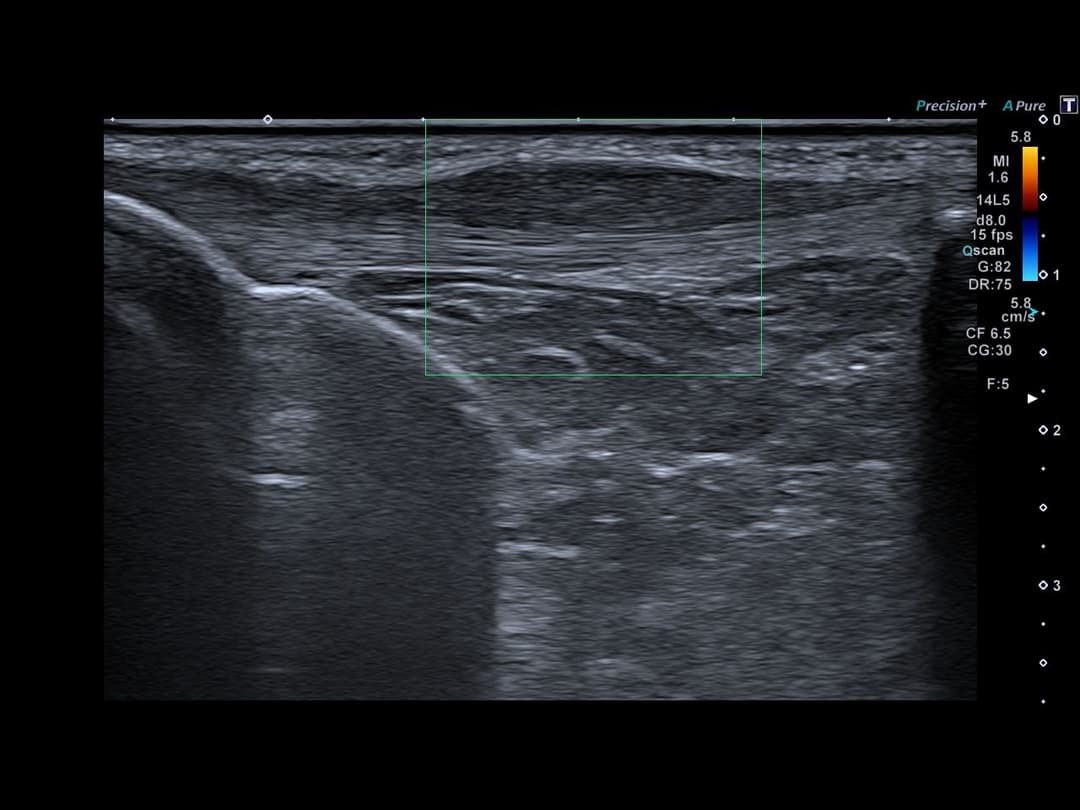

Tendinopathie patellaire corporéale superficielle

Epaississement fusiforme avec hypo échogénicité de la portion corporéale superficielle du tendon patellaire, étendue sur 3cm de hauteur, sans fissuration intra-tendineuse notable.

Discret œdème des tissus mous cellulo-graisseux sous-cutanés adjacents.